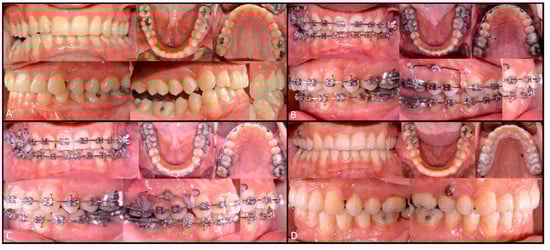

- Decompensating orthodontic treatment

- Orthodontic refinement treatment

2.1. First Step

2.2. Second Step

2.3. Third Step